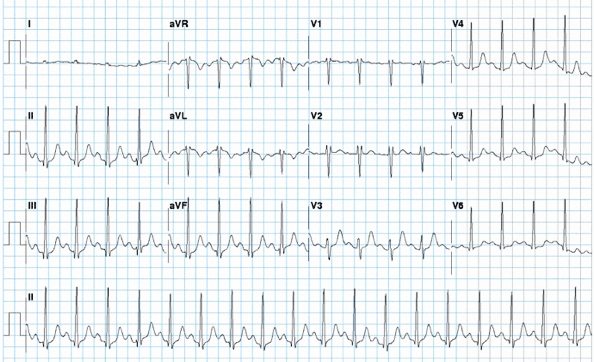

Resting ECG shows delta waves (red arrows) in the inferior and lateral leads

From the collection of Dr Mithilesh K. Das